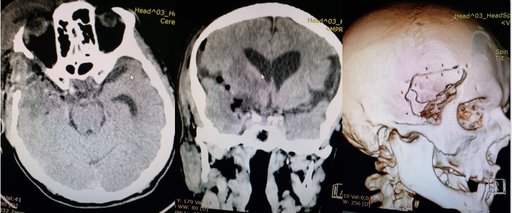

Пацієнт житель м. Тернополя звернувся з скаргами на постійний головний біль, зниження гостроти зору, головокружіння, періодичну нудоту, неконтрольований сечопуск, фокальні епінапади. Проведено дообстеження МРТ голови з контрастуванням (1,5 Т), КТ голови з контрастуванням для виявлення локалізації та співвідношення до оточуючих структур, кровопостачання пухлини.

Пухлина видалена тотально (в товщі пухлини проходили передня та середня мозкові артерії, задня сполучна артерія та передня хоріїдальна артерія), також виконана декомпресія канала зорового нерва. Для адекватного доступу використовувався Neuro High Speed Drill краніотом з мікробороми.

Післяопераційний період без особливостей, симтоматика регресувала, пацієнт в задовільному стані виписаний.